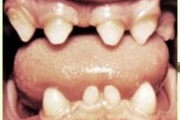

Lutipudelikaaries